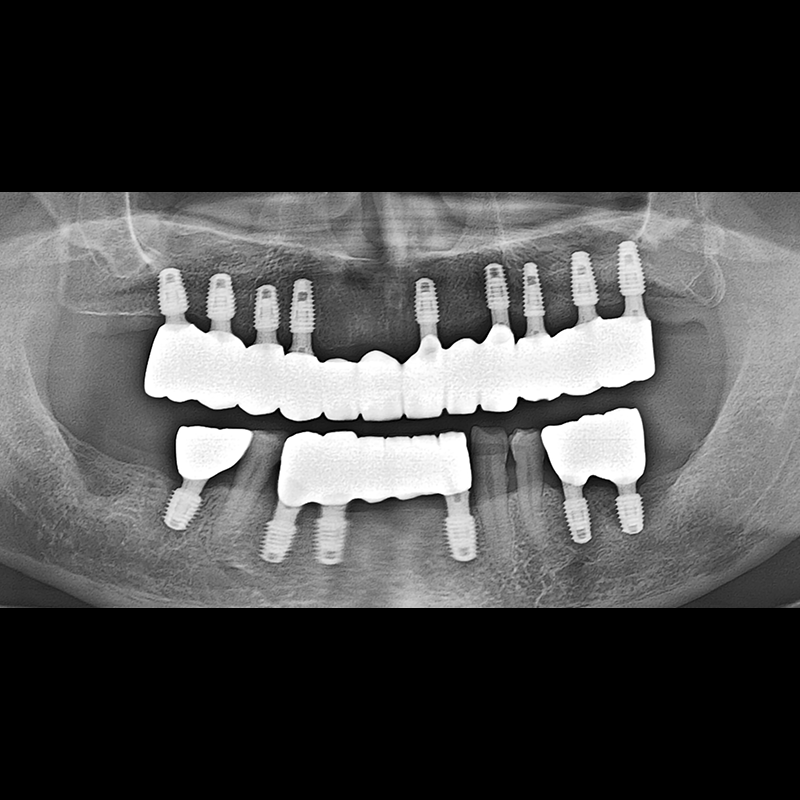

BEFORE AFTER

Implant before and after 2025.05.30

Implants were placed in the missing tooth and in the tooth position where it was difficult to save.